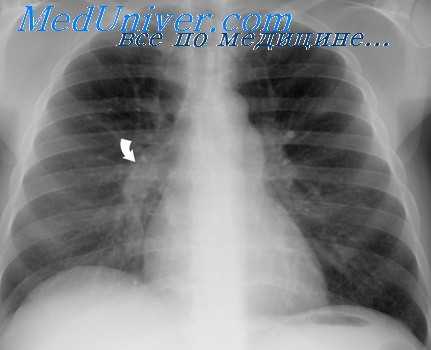

На ЭКГ при митральной регургитации могут наблюдаться признаки увеличения левого предсердия и гипертрофии левого желудочка, а также признаки мерцательной аритмии. При выполнении рентгенографии грудной клетки могут наблюдаться признаки застоя в малом круге кровообращения, увеличения левого предсердия и левого желудочка, а при развитии легочной гипертензии – правых отделов сердца.

Диагноз подтверждается данными рентгенологического и инструментальных методов исследования: фонокардиографией, электрокимографией, реовазографией и катетеризацией полостей сердца (Rudolf, Cayler, 1958; В. И. Бураковский, Б. А. Константинов, 1964; Ю. Д. Волынский с соавт., 1967, и др.).